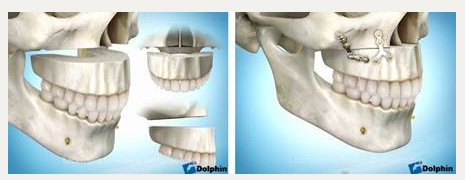

Остеотомия верхней челюстиПоказания Коррекция аномалий развития верхней челюсти (микрогнатия, ретрогнатия верхней челюсти). Остеотомию на верхней челюсти проводят как этап ортодонтического лечения. Операция Остеотомия верхней челюсти выполняется внутриротовым доступом под эндотрахеальным наркозом, выполняется разрез слизистой оболочки полости рта и надкостницы, разрез производят несколько выше переходной складки верхней челюсти от 7 до 7 зубов. Края раны раздвигаются, тем самым осуществляется доступ к передней стенке верхней челюсти.  На передних и боковых стенках верхней челюсти слева и справа производятся разметки линий распилов.  Специальными пилками проводится остеотомия по разметкам.  Затем отделяется распиленный фрагмент и перемещается в заранее выбранное положение.   Фиксация перемещенного фрагмента в новом положении осуществляется титановыми мини-пластинками.  Длительность Операция занимает от 1,5 до 3 часов и проводится под наркозом. В течение 1 месяца после лечения сохраняется отечность мягких тканей лица, может отмечаться нарушение чувствительности верхней губы и щек, чувствительность восстанавливается самопроизвольно через некоторое время. В ряде случаев после операции для обеспечения хорошего срастания костей проводят межчелюстное шинирование , верхняя и нижняя челюсти фиксируются друг к другу специальными приспособлениями, так что полное открытие рта невозможно. В этот период (2-3 недели) возможно питание только протертой и жидкой пищей. После операции остеотомии верхней челюстиВ послеоперационном периоде возможно ношение ортодонтической брекет системы для правильного смыкания зубных рядов верхней и нижней челюстей. Реабилитационный период В течение 1-3 суток после операции рекомендовано нахождение в стационаре под наблюдением медицинского персонала (длительность нахождения в стационаре может быть продлена до 10 суток в зависимости от течения послеоперационного периода). Длительность реабилитационного периода зависит от восстановительных способностей организма. Эффективность Окончательный результат операции можно наблюдать через 3-6 месяцев. В послеоперационном периоде могут сохраняться отеки в течение 2-4 недель, в зависимости от индивидуальных особенностей восстановление протекает с разной скоростью. |